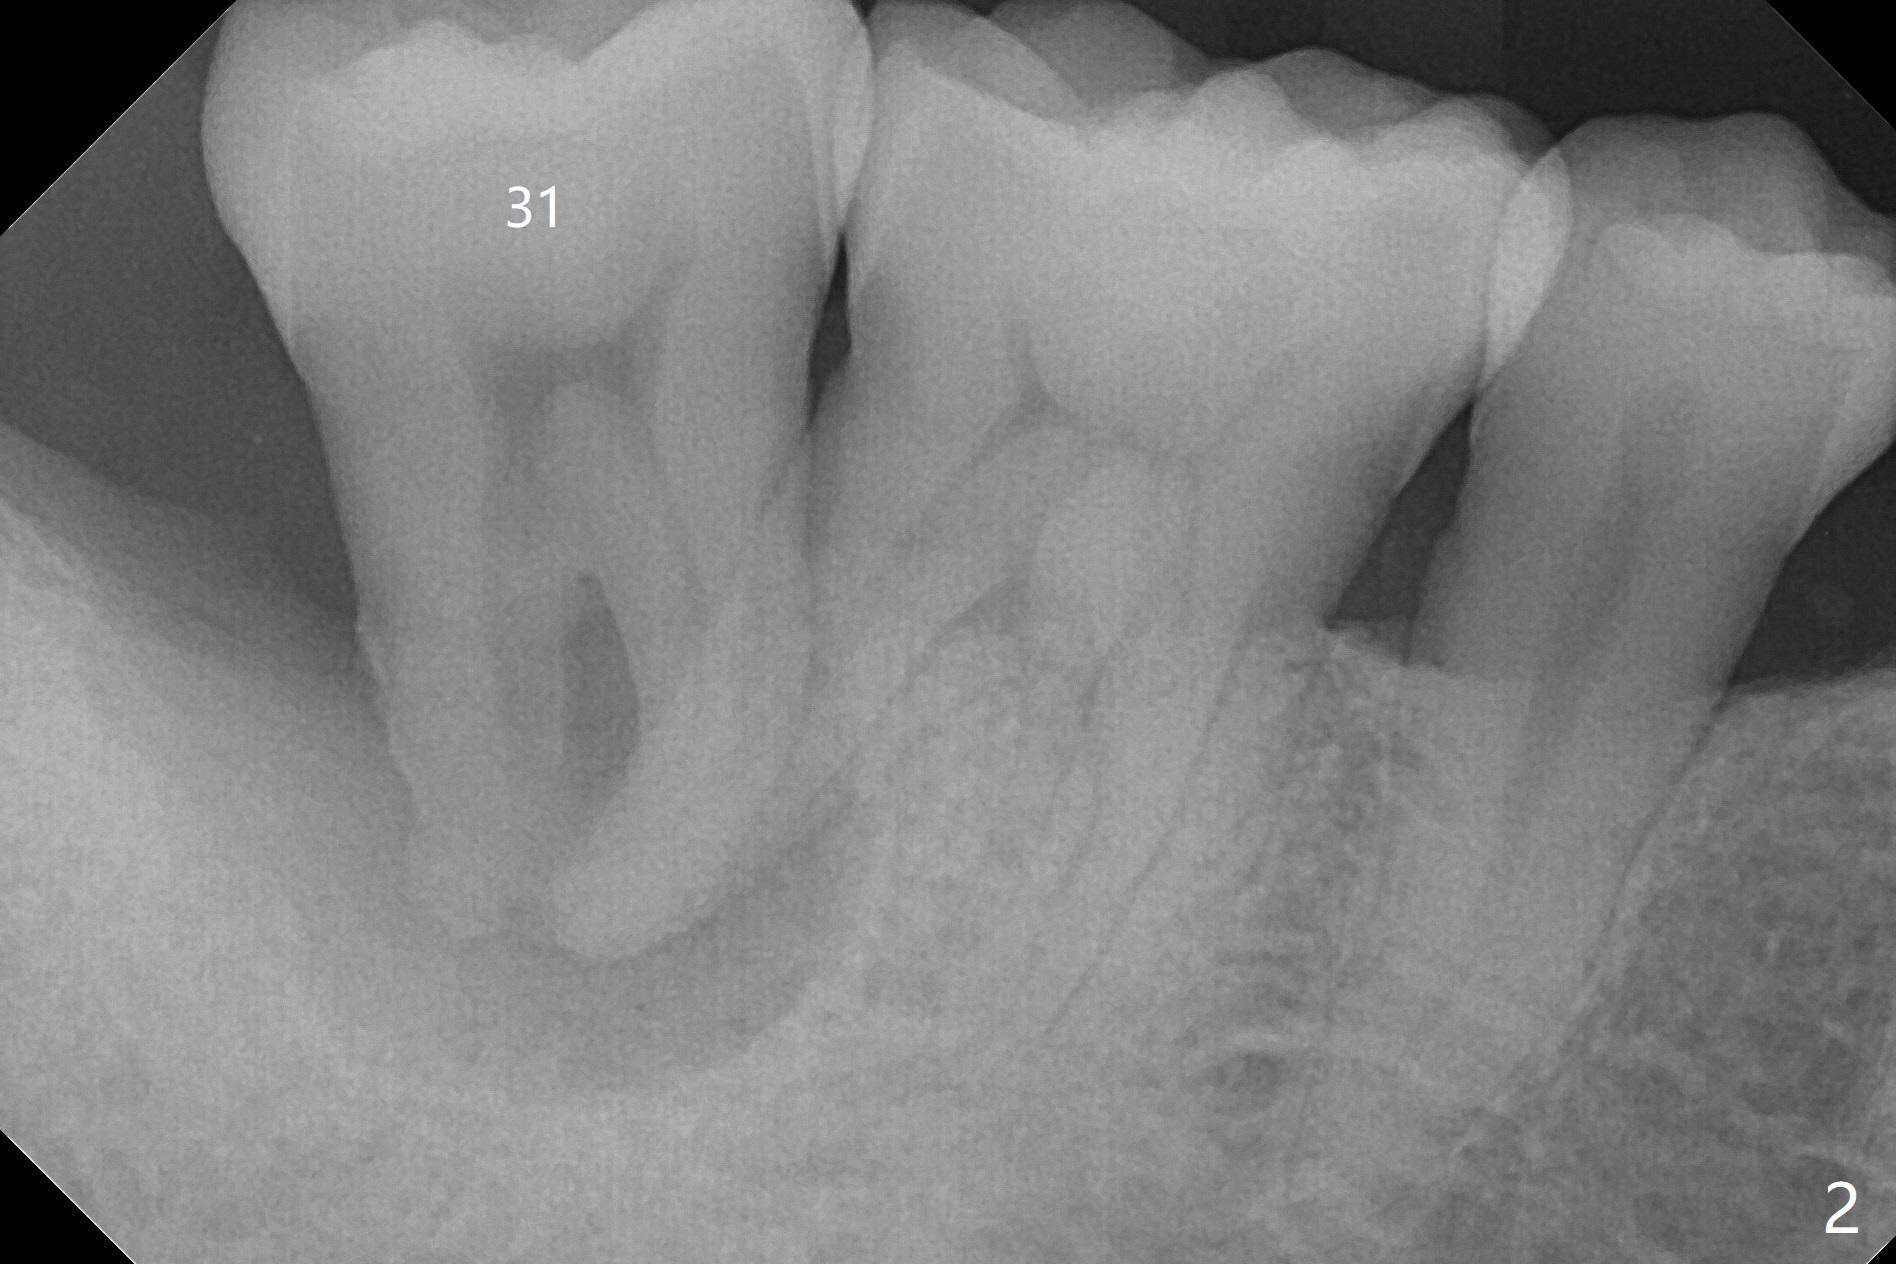

A 47-year-old man, a possible bruxer (Fig.1), is concerned about the mobile 2nd molar and lower central incisor (Fig.2,3). To prevent periimplantitis, a 2 mm 1-piece implant and a short one (5x5 mm) will be placed subcrestal at these sites, respectively (Fig.4,5). Sticky bone is a must. Pulpal test will determine whether RCT is required for #30 (Fig.5 curved white line). In fact the tooth #30 is tested to be vital. Onlay graft is an option for #31 (Fig.6 red rectangle). There is history of #32 extraction. The severely periodontally affected tooth #25 (Fig.7 *) has narrow mesiodistal space (Fig.8). It is the best treated with extraction with bone graft and self drifting.